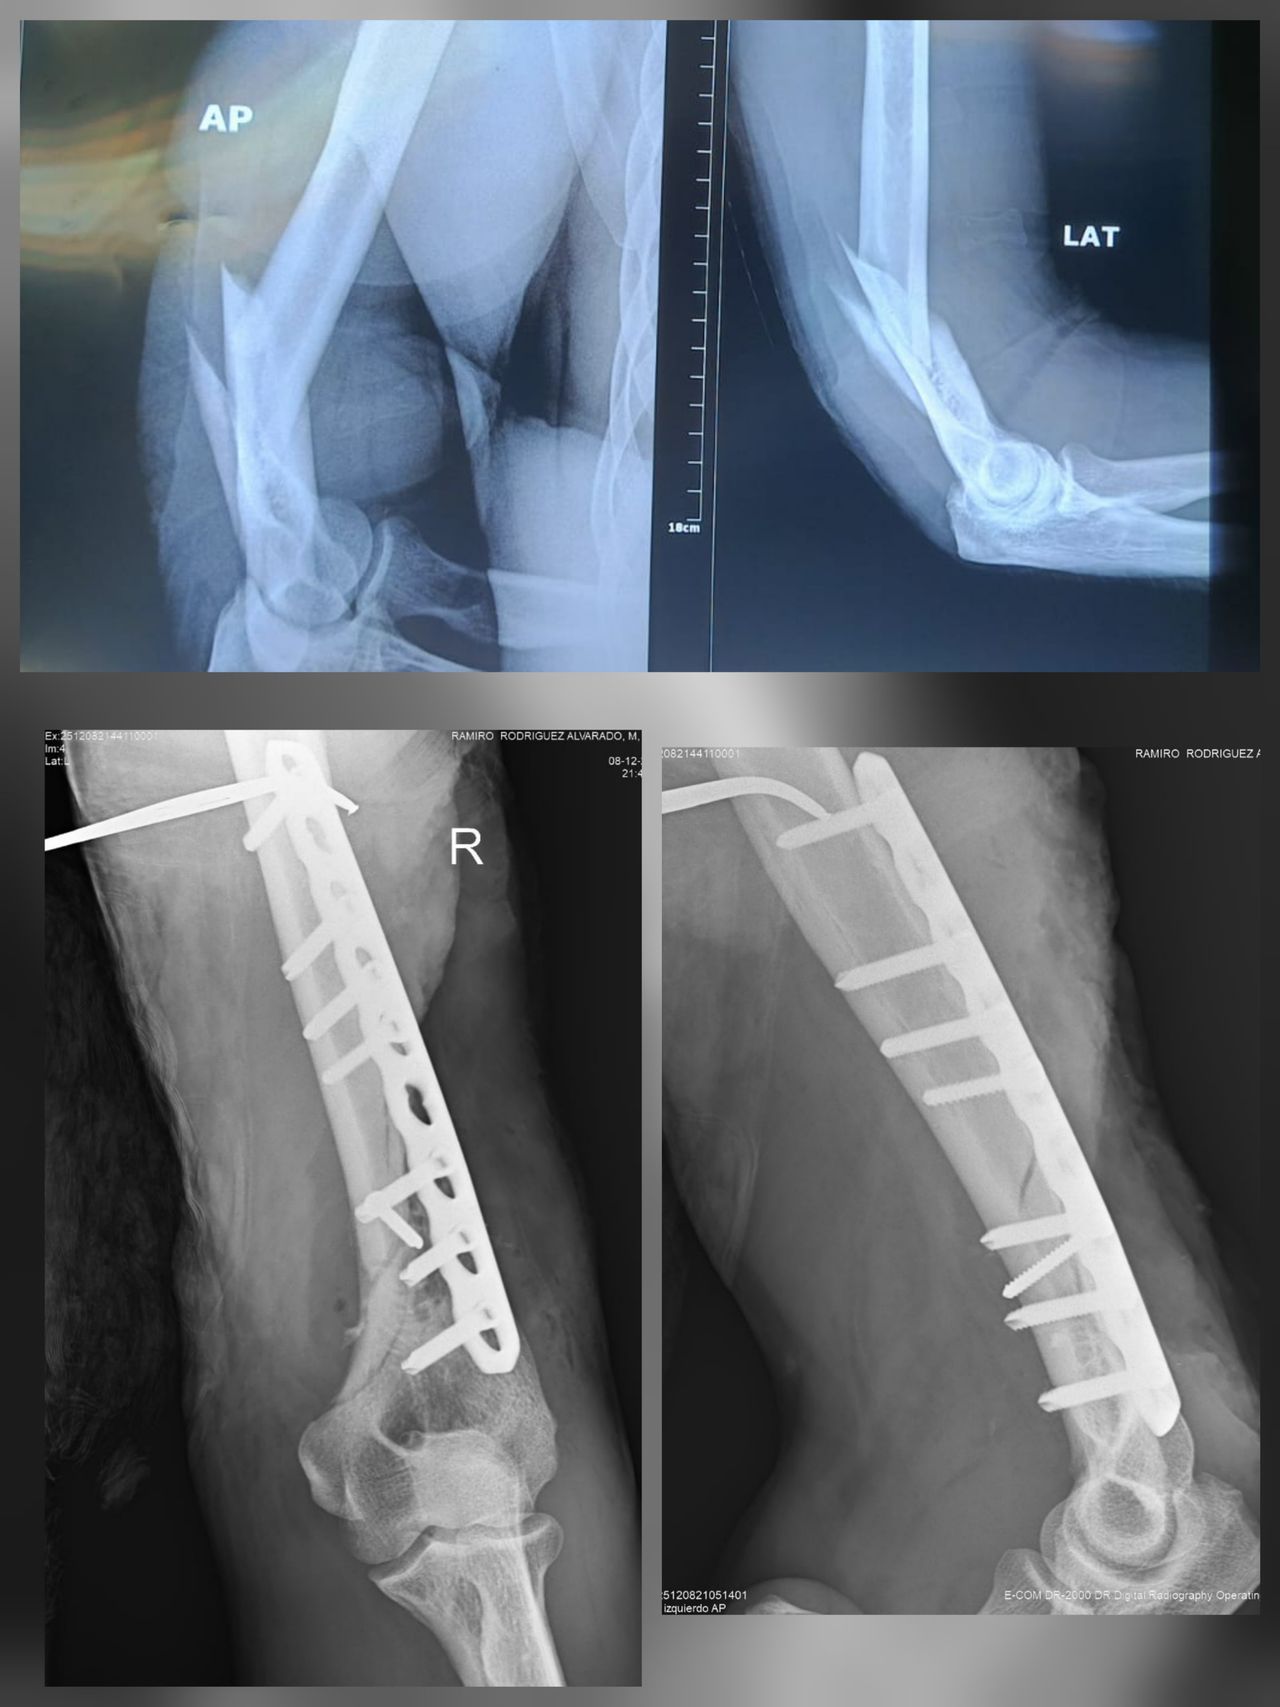

Mis habilidades más fuertes son el manejo de padecimientos de rodilla, cadera y hombro, así como procedimientos quirúrgicos asociadas a enfermedades degenerativas, fracturas y luxaciones.